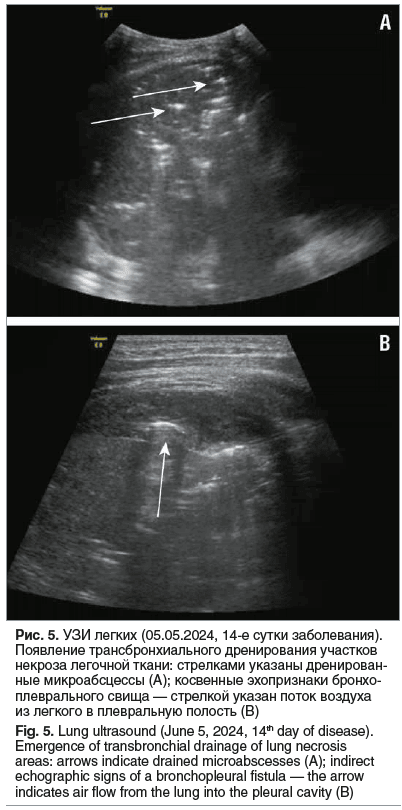

05.06.2024 (14-е сутки заболевания) при УЗИ ОГП определялись множественные (без счета) включения газа 5–7 мм в диаметре во всех отделах легкого, сохранялись единичные недренированные зоны деструкции (рис. 5А). В нижнебоковом отделе достоверно прослеживалось формирование бронхоплевральных свищей (рис. 5В). Таким образом, повышение лабораторных маркеров воспаления было ассоциировано с начинающимся трансбронхиальным дренированием очагов некроза и формированием свищей. В связи с массивным сбросом воздуха по плевральному дренажу 10.06.2024 в правый главный бронх был установлен бронхоблокатор.